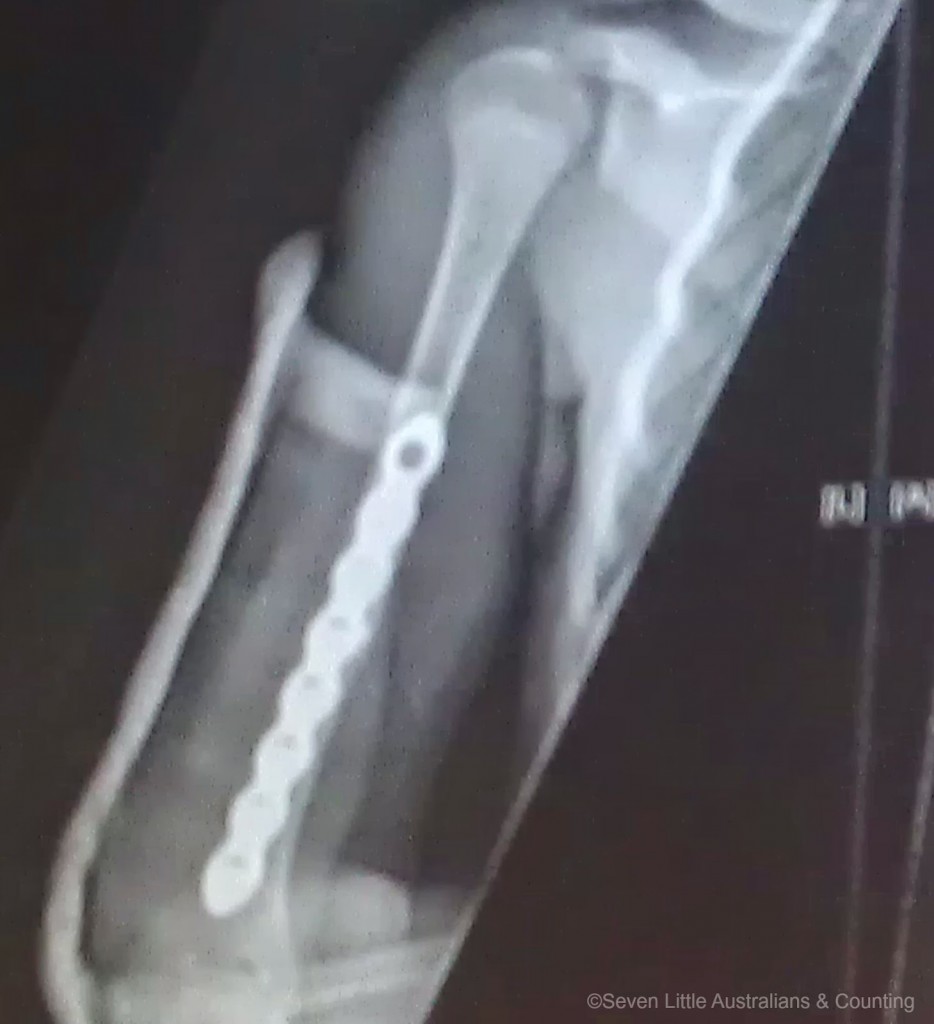

The surgery was successful and the surgeon was extremely happy with his handiwork, the plate and screws lined the bone up nicely. The surgeon was rather young and when he invited me to look at the x-rays, he rather made me smile, he was quite chuffed with his handiwork, but then he had every right to be proud. Generally surgery to repair a ten year old’s humus bone is not necessary but due to the break in this case it was decided it was, as it transpired, it was the correct decision as when they went in it was discovered that her radial nerve was stretched over the ragged edges of the bones.